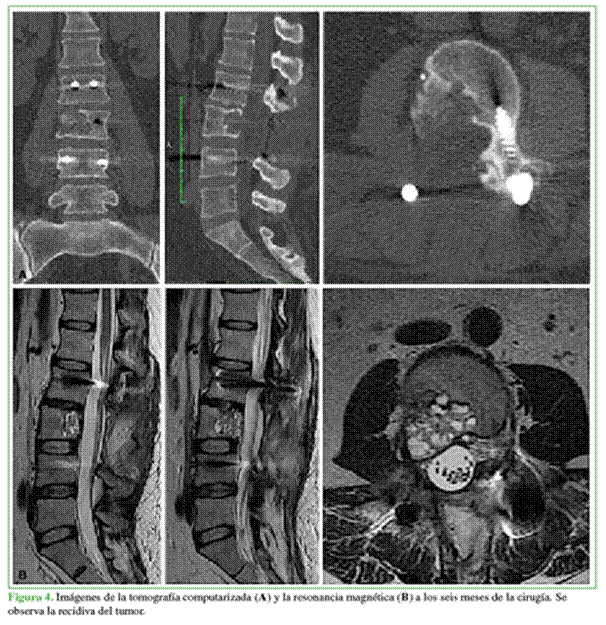

A los seis meses del procedimiento, la paciente no tiene síntomas. La tomografía computarizada y la resonancia magnética de control (Figura 4) muestran una imagen compatible con recidiva local del QOA. Después de consultar la bibliografía citada en este artículo, se discutió el nuevo tratamiento con las siguientes opciones: nueva vertebrectomía de L3, inyecciones intratumorales de corticoides y calcitonina, embolización del tumor, administración de denosumab. Se optó por el tratamiento con denosumab 120 mg, dosis inicial, cada tres meses, por dos años. A medio término se realizó un control tomográfico y se constató la remisión y la calcificación de la lesión (Figura 5).